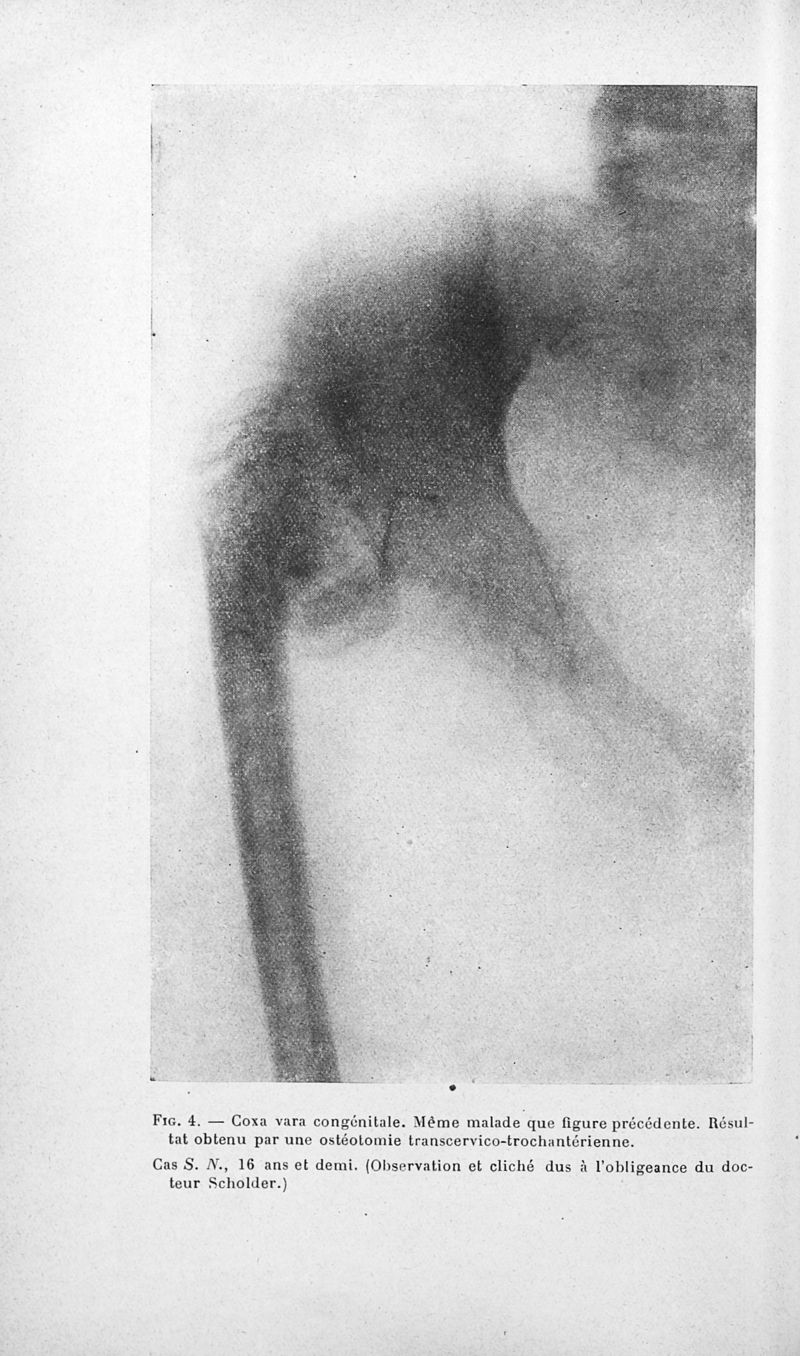

Bulletins de la société de pédiatrie de Paris

Tome vingt-septième. - Paris : Masson et Cie, 1929.